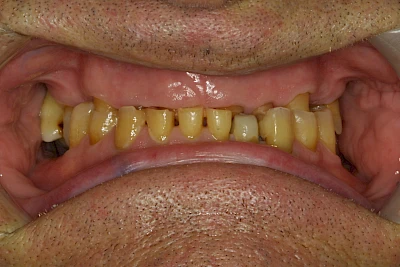

Über die Zeit können verschiedene Prozesse die Zahnhartsubstanzen aufzehren:

- Abnutzung durch Kauen (Abrasion) oder duch durch übermäßiges Knirschen bzw. Pressen (Attrition)

- Säurebedingte Auswaschung (Erosion)

- Knirschen bzw. Pressen und ungünstige Putztechnik (Druck): keilförmige Defekte

Die Zähne können dabei auf Reize (warm, kalt, süß, sauer) oder auch beim Zähneputzen empfindlich oder schmerzhaft sein. In allen diesen Fällen ist es sinnvoll, den Zahnarzt zu kontaktieren und das weitere Vorgehen abzustimmen.